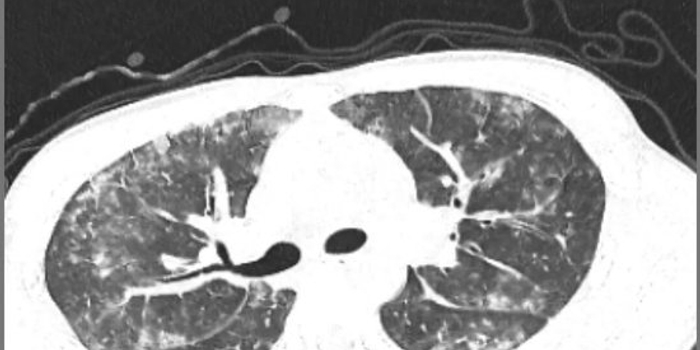

6天胸闷气短、5天持续高热,18岁的小宋被紧急送入平原县人民医院呼吸内科,胸部CT检查结果让接诊医生忧心不已,双肺布满大片“毛玻璃”阴影,呈现弥漫性病变,提示肺部正遭受严重侵袭。更棘手的是,常规感染筛查中,细菌、病毒等常见病原体检测均为阴性,病因成谜,治疗陷入困境。

诊断明确后,呼吸内科医师团队制定了针对性极强的精准治疗方案。令人惊叹的疗效随之出现,在针对性药物治疗仅5天后,患者复查胸部CT。影像对比显示,原本遍布双肺的弥漫性“毛玻璃”阴影已基本完全吸收